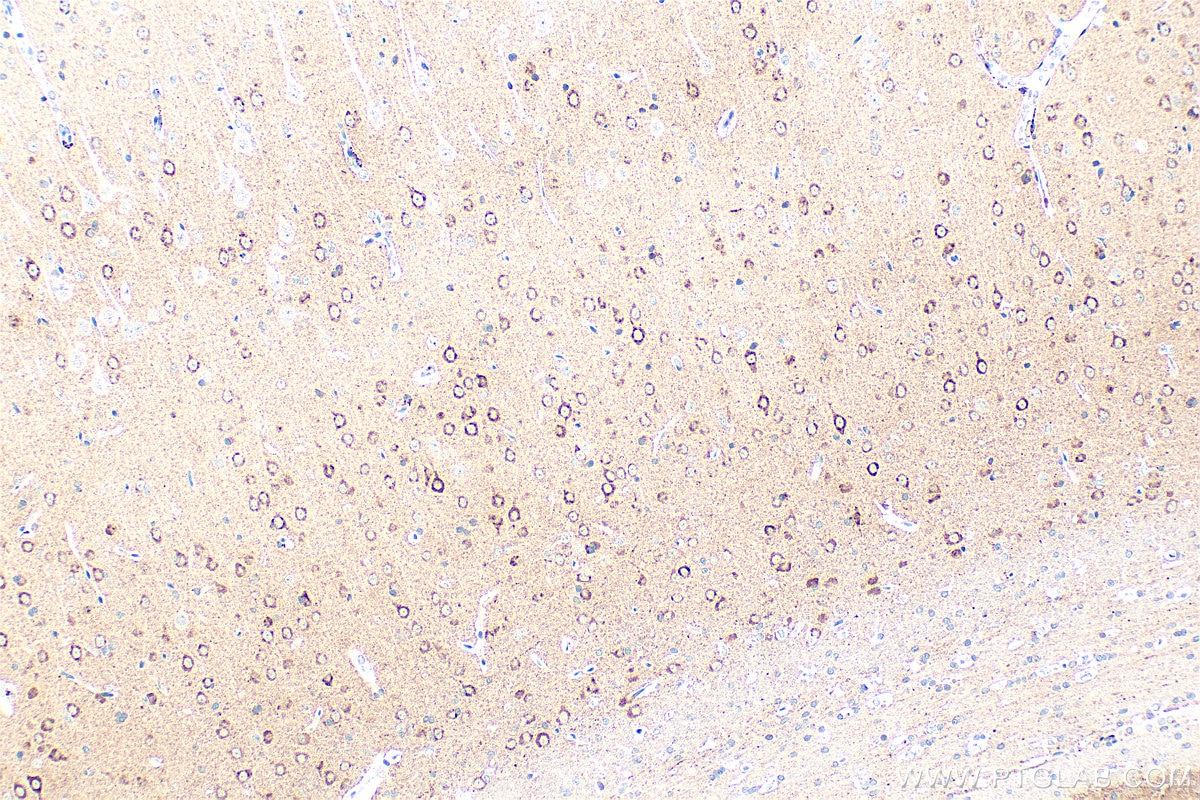

| Positive IHC detected in | human brain tissue, human pancreas cancer tissue, rat brain tissue Note: suggested antigen retrieval with TE buffer pH 9.0; (*) Alternatively, antigen retrieval may be performed with citrate buffer pH 6.0 |

| Immunohistochemistry (IHC) | IHC : 1:50-1:500 |

10889-1-AP targets NPTX2 in WB, IHC, IF/ICC, IP, CoIP, ELISA applications and shows reactivity with human, mouse, rat samples.